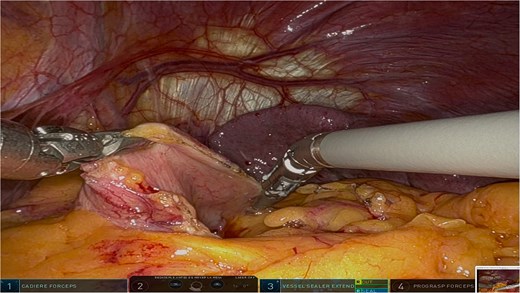

The surgery was performed using the Da Vinci robotic system under general anesthesia. The patient was positioned supine with reverse Trendelenburg. Four robotic trocars and one assistant trocar were placed. The gastro-splenic ligament was dissected to expose the distal pancreas, and the pancreas was transected using a linear stapler, ensuring tumor-free margins (Fig. 2). The splenic artery and vein were individually ligated with robotic sutures, and the spleen was mobilized and removed along with the pancreas (Fig. 3). The specimen was extracted via mini-laparotomy and sent for histopathological analysis (Fig. 4).

Intraoperative view showcasing the dissection and mobilization of the greater curvature of the stomach. This involved dividing the gastrocolic ligament to expose the retroperitoneal space, providing access to the distal pancreas while preserving surrounding structures to minimize surgical trauma.